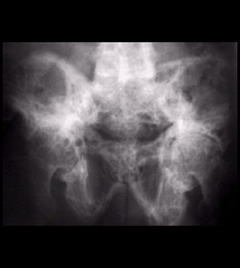

Pelvis

Figure 4: Paget's disease of the pelvis. The bone is thick, wide and patchy.

Paget’s disease of the pelvis. The bone is thick, wide, and patchy.